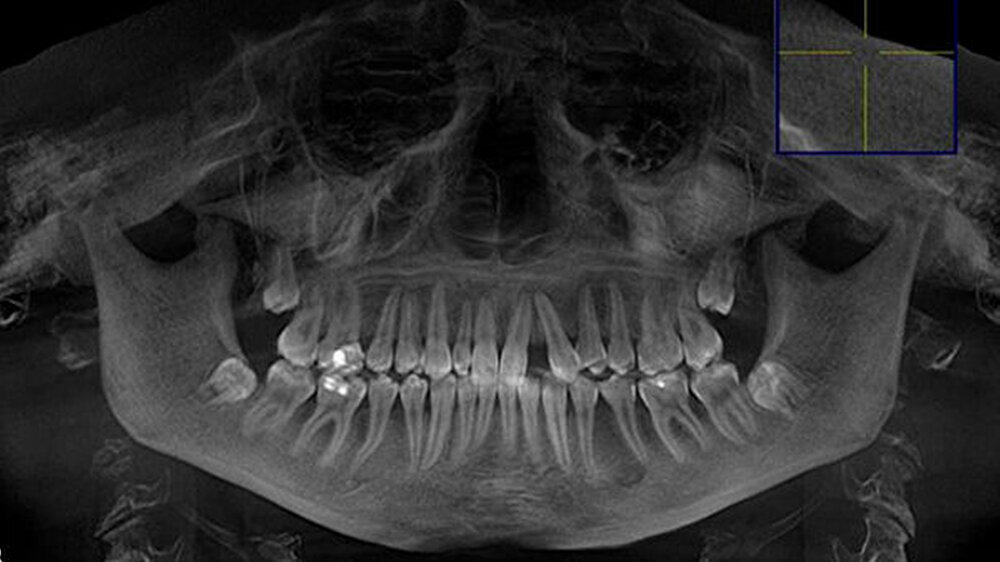

Eine 20-jährige Patientin stellte sich erstmalig zur Implantat- und Distraktionsberatung in unserer Abteilung für Mund-, Kiefer- und Gesichtschirurgie vor. Diagnostisch lagen eine mandibuläre Retrognathie, retinierte und verlagerte Zähne 18, 28, 38 und 48, ein Zapfenzahn 12, ein fehlender Zahn in regio 022, eine Mittellinienverschiebung und ein Engstand der Oberkieferfront vor (Abbildungen 1a bis d). Im Rahmen der klinischen Untersuchung und basierend auf dem Auswertungsergebnis der Digitalen Volumentomografie (DVT) führten wir bei der Patientin im Hinblick möglicher therapeutischer Maßnahmen eine differenzial-therapeutische Beratung durch.

Klinisch als auch radiologisch lag eine konvergierende Wurzelstellung der Zähne 21 und 23 vor. Eine unkomplizierte implantatprothetische Versorgung der Lücke 022, das heißt ohne Verletzung der benachbarten angulierten Zähne, erschien nicht möglich. Die Schwierigkeit bestand darin, die Lücke 022 durch körperliche Bewegung der Zähne zu öffnen, was sich bislang mittels festsitzender Apparatur als frustran erwiesen hatte. Der Patientin wurde aufgrund der vorliegenden Diagnose eine parodontal akzelerierte osteogenetische Orthodontie (PAOO) im Bereich des linken Oberkiefers empfohlen.